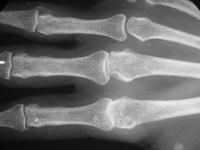

Clinical Example: Pyrolytic carbon metacarpophalangeal joint implant arthoplasty

Pyrolytic carbon implant arthroplasty of the finger joints appears to be an improvement on previous strategies, as it mimics the normal joint mechanics, in movement, lack of wear debris and a close match to the mechanical characteristics of the finger bones.

Pre and postop radiographs.